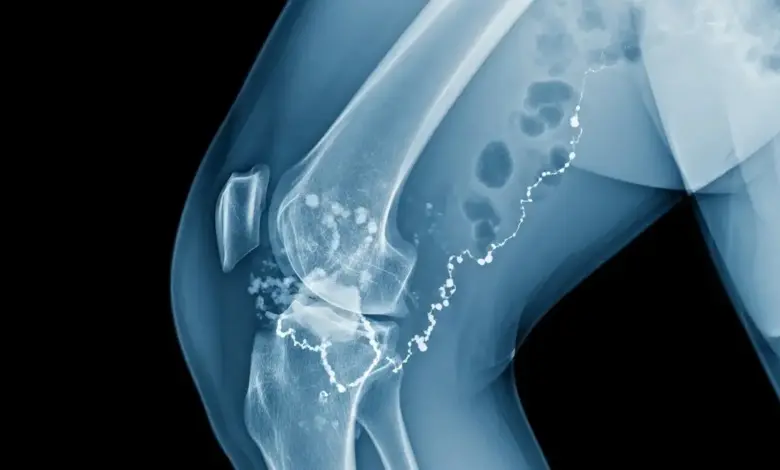

Na osteomielite subaguda do joelho, o problema atinge o osso ao redor da articulação, com foco mais frequente na metáfise distal do fêmur e na metáfise proximal da tíbia.

- Radiografias em diferentes incidências, que podem ser normais no início ou revelar áreas de rarefação e esclerose ao longo das semanas;

- Ressonância magnética, exame mais sensível para edema da medula óssea, coleções e acometimento de partes moles;

- Tomografia computadorizada para detalhar cavidades ósseas, abscesso de Brodie e planejar eventual cirurgia.